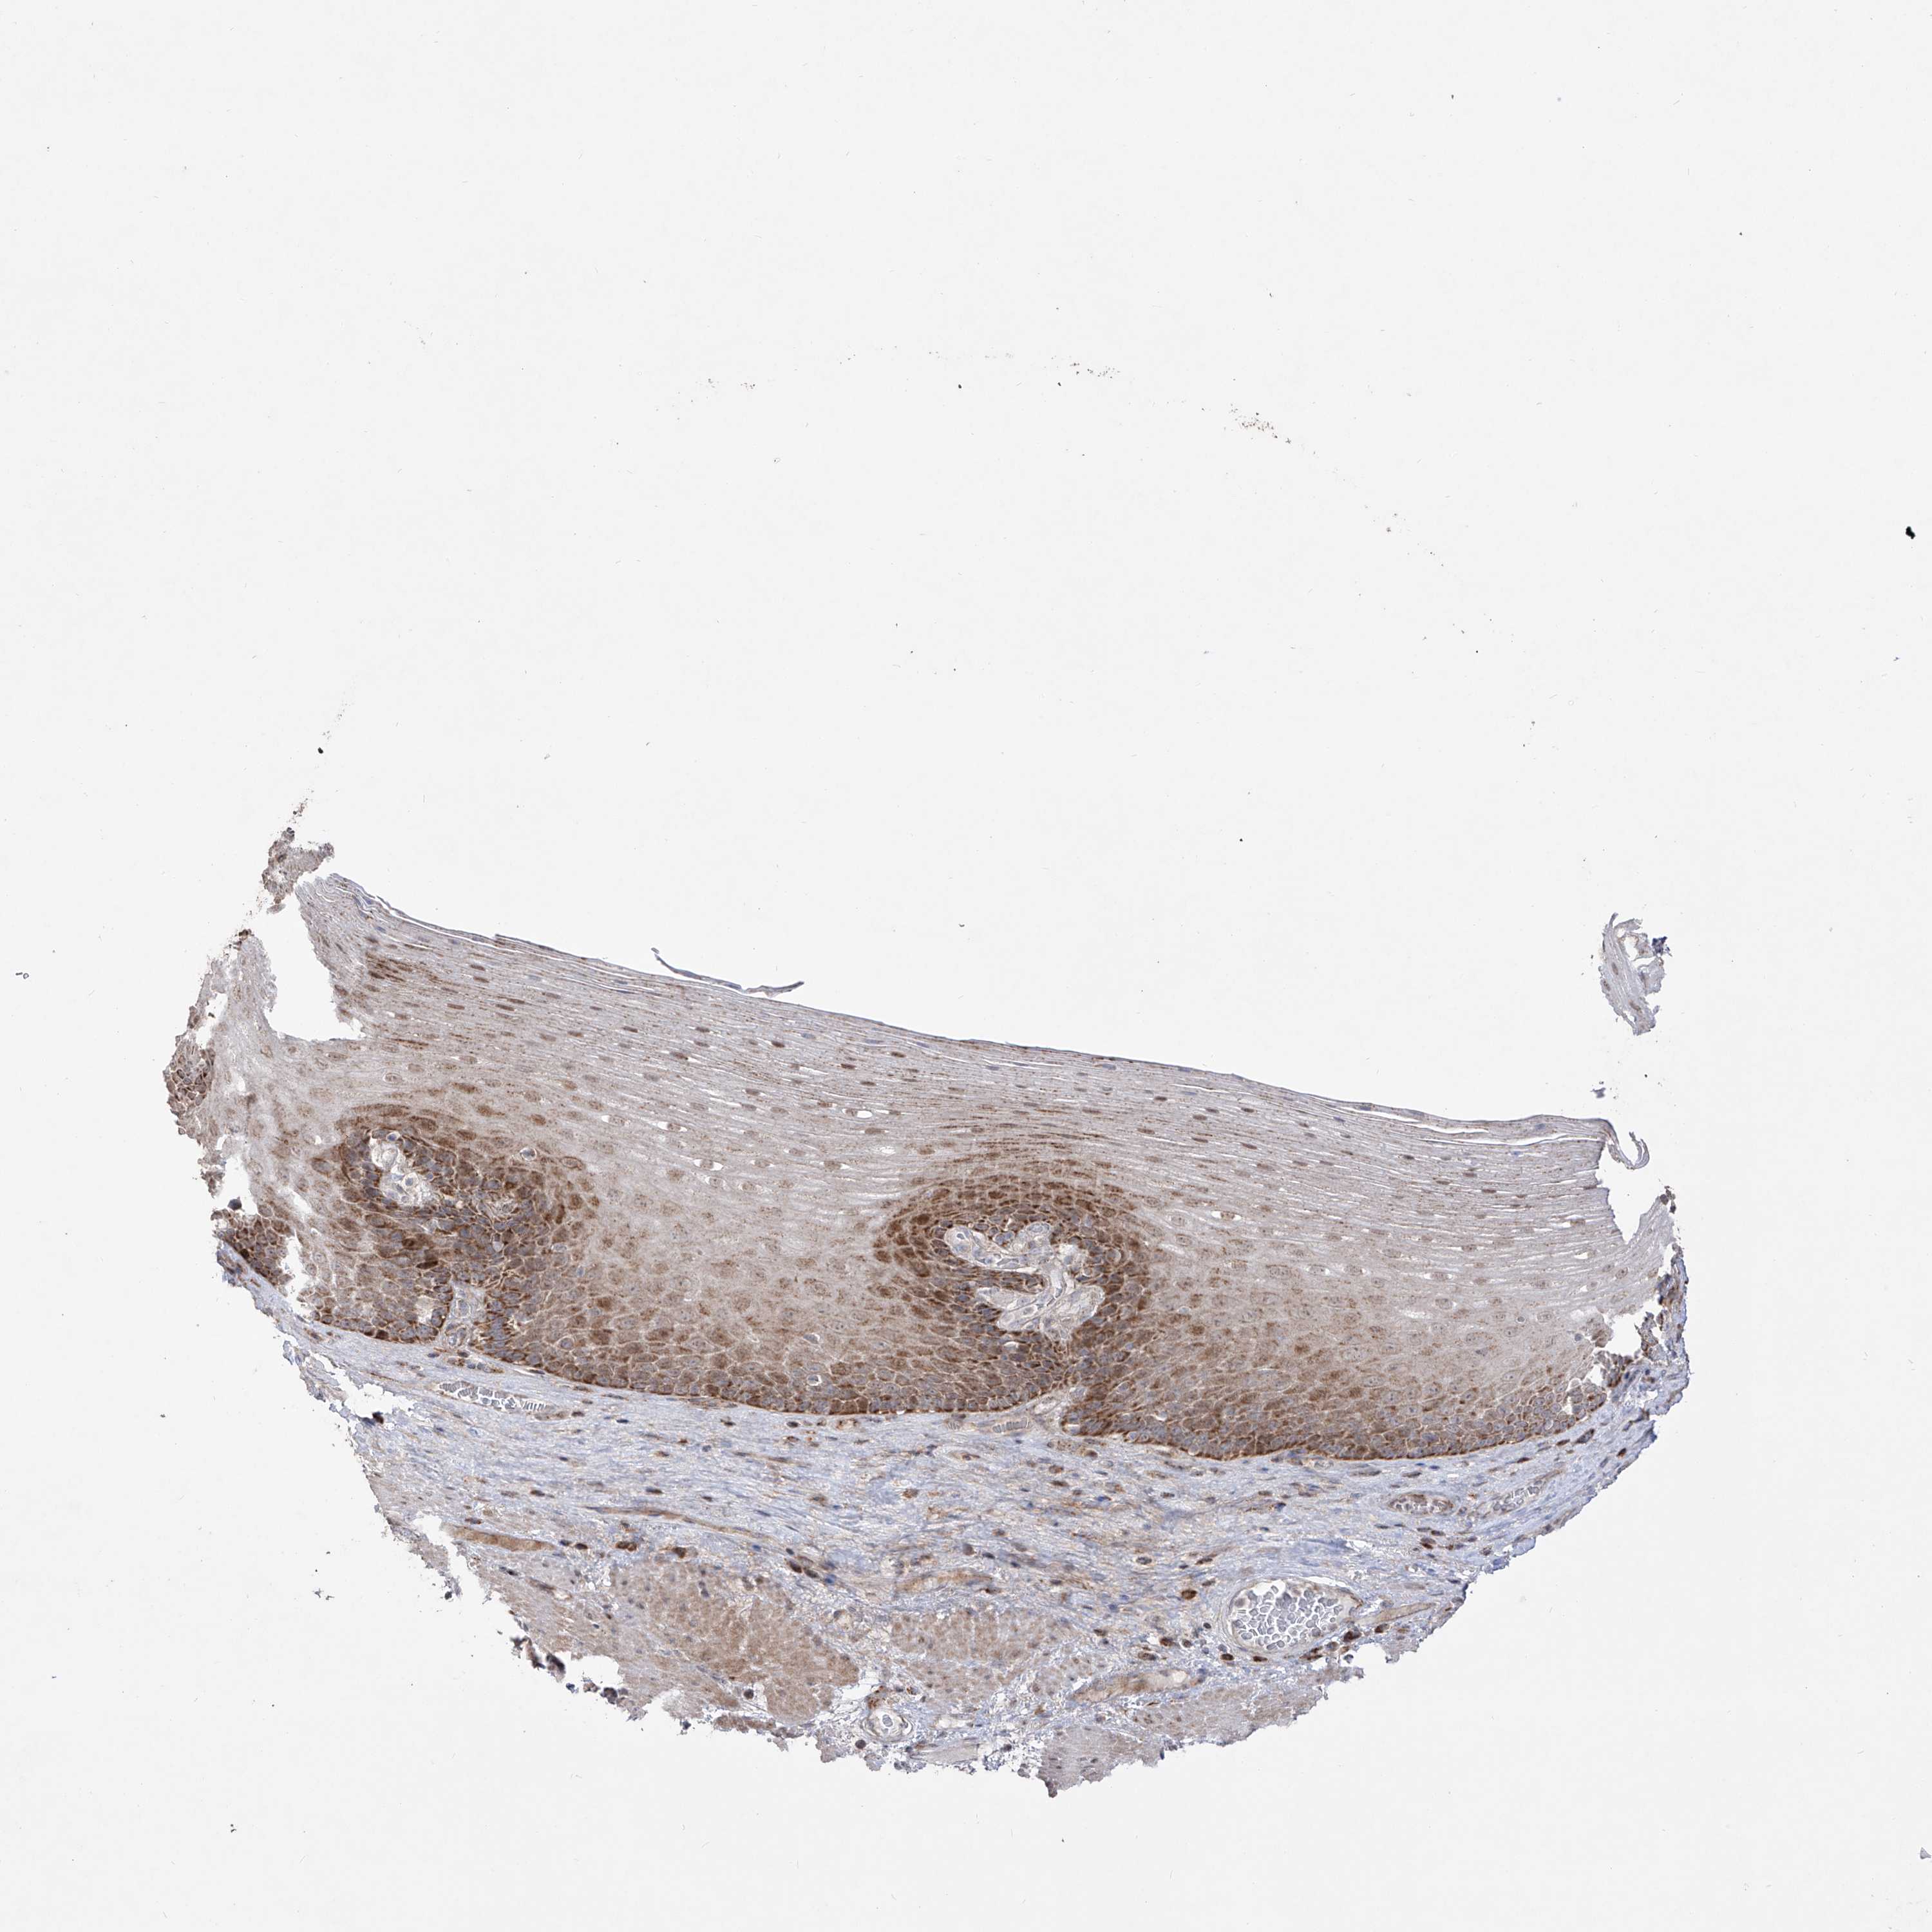

ESOPHAGUS - Antibody stainingi

Antibody staining in the annotated cell types in the current human tissue is reported as not detected, low, medium, or high, based on conventional immunohistochemistry profiling in selected tissues. This score is based on the combination of the staining intensity and fraction of stained cells.

Each image is clickable and will lead to virtual microscopy that enables deeper exploration of all samples and also displays staining intensity scores, fraction scores and subcellular localization as well as patient and tissue information for each sample.

Antibody HPA030817Antibody HPA030818

Squamous epithelial cells MediumMedium